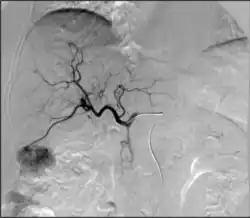

Takayasu arteritis angiography

Dissections can also arise in virtually any other artery. Carotid artery dissection, for example, places patients at increased risk for stroke and may extend further into the blood vessels within the brain. Vertebral artery dissection are less common but also dangerous for similar reasons. Mesenteric artery dissection may limit the blood supply to the intestines. Renal artery dissections can decrease blood flow to the kidneys and contribute to hypertension.[94] Peripheral arterial dissections can be found elsewhere in the arms and legs. These dissections can occur primarily due to focal traumas, underlying vascular disease, or as an extension of a larger, complex aortic dissection that tears further into these smaller branches.